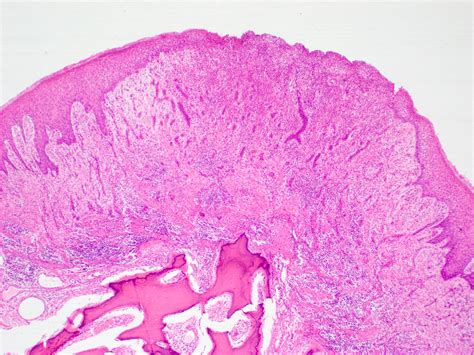

In most cases, a clinical diagnosis is sufficient. However, if the lesion appears atypical, grows rapidly, or has an unusual appearance, the dentist may recommend an excisional biopsy. This is a simple procedure where the tissue is removed and sent to a laboratory to be examined under a microscope by a pathologist. This is a standard precautionary measure to ensure the lesion is indeed benign.

• oral fibroma pathology outlines